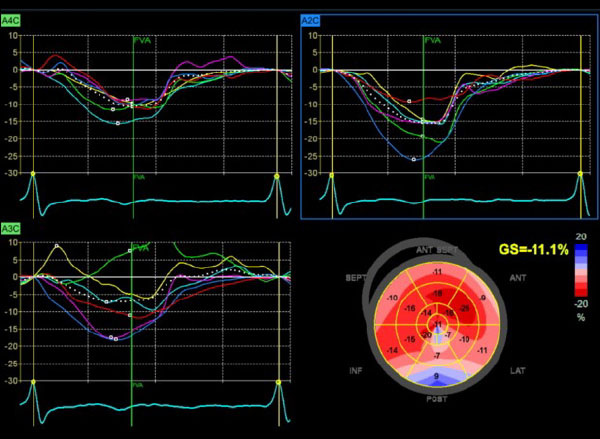

Figure 3 : altération du strain basal dyskinésie apicale

- Phénotype typique : petite cavité VG, hypertrophie modérée, dilatation OG sévère, profil mitral, VCI dilatée

- Encore une fois l’aspect écho est typique d’une CMR